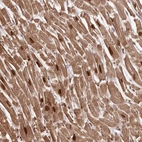

Immunohistochemical staining of human heart muscle shows strong nuclear and moderate cytoplasmic positivity in myocytes.